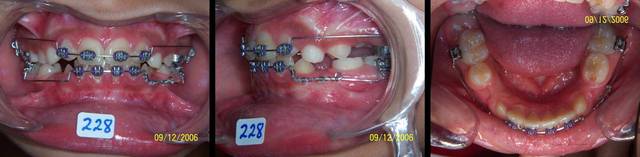

Voici un cas qui ressemble un peu a ton cas, en moins grave, mais qui peut te donner une idee sur ce qu'il faut faire.

Mon patient, ou plutot les parents, n'etaient pas tres cooperants, manquaient pas mal de RDV, et je n'ai plus revu a la fin de traitement. Ici a Abu Dhabi il en a pas mal comme ca!!

Bref, le systeme de MacAndrews peut etre utile dans ces cas. Un arc de base de stabilisation basic, jambe du cote de la deviation contre la laterale, le cote oppose est a distance pour permettre le mouvement des 4 incisives. Une boucle au milieu du pont lateral sert de stop pour le ressort active de la quantite de deplacement desiree avec 3 mm de plus et insere pendant la fabrication de l'arc de base. On laisse faire le systeme tout seul.